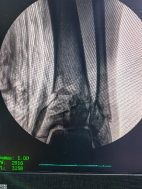

透視檢查骨折端

控制機器人牽引斷端,可見關(guān)節(jié)間隙恢復。